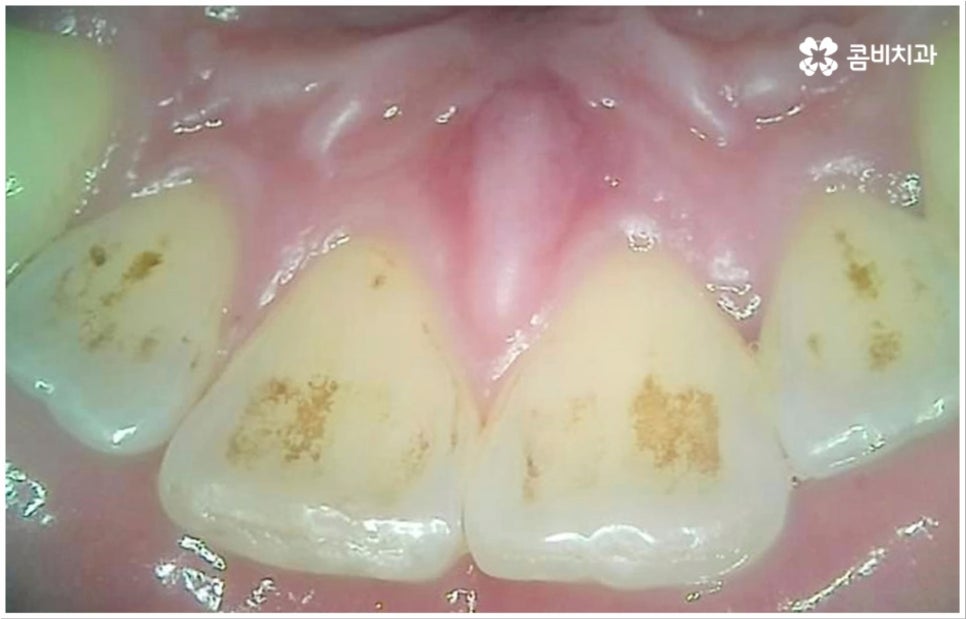

흔히 치과를 찾게 되는 원인 중 하나인 충치는 보통 위아래 치아가 맞닿는 교합면, 즉 우리가 식사를 할 때 음식물을 잘게 자르고 갈아주는 역할을 하는 씹는면에 발생할 가능성이 가장 크다고 할 수 있습니다. 그 이유는 교합면의 모양을 생각해 보면 잘 알 수 있는데요. 한 예로 우리가 거울 앞에서 입을 크게 벌렸을 때 쉽게 살펴볼 수 있는 아래 어금니의 교합면을 생각해 보면 윗면이 평평한 게 아니라 볼록하게 올라온 부위(교두)와 그 사이의 깊은 홈(구)으로 이루어져 있기 때문에 식사 후 치아 사이나 이 홈 부분에 음식물 찌꺼기나 침 등이 잔존할 가능성이 많은데, 이를 깨끗하게 제거해 주지 않으면 여기서 세균이 급증하여 충치 등 구강 질환이 발생할 빈도수도 높아지게 되는 거예요.

이러한 교합면 충치는 비교적 관찰이 쉽고 접근 역시 용이하기 때문에 조금만 주의를 기울이면 충분히 예방 또는 초기 치료를 할 수 있습니다. 물론 완전 초기 단계에서는 신경이 없는 치아 겉면인 법랑질부터 우식이 일어나기 때문에 충치 통증 도 거의 없고 육안으로 구별해 낼 수 있는 특징 (색깔 변화 등) 도 미미하므로 환자분들의 입장에서 충치가 발생했다는 것을 인지하기 어려울 수 있어요. 이와 같이 자기도 모르게 발생했을지 모를 충치에 대해 예방 및 조기 대처를 하기 위해서는 1년에 한 번 또는 두 번 정도 치과에 정기적으로 내원하셔서 꼼꼼하게 검진을 받으시는 것이 구강 건강을 지키기 위한 보다 바람직한 방법이 될 거예요.